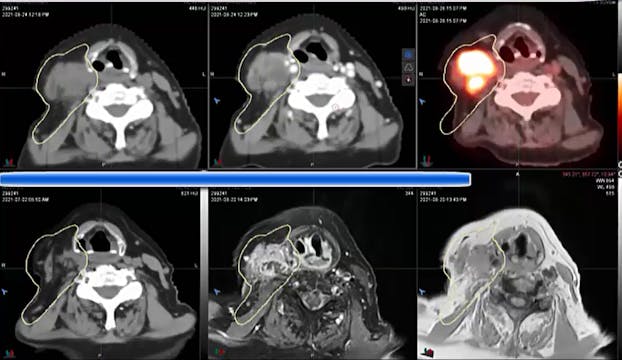

06/28/2021 Dr. David Sher - Radiation Oncology - Head & Neck

malignant melanoma, treatment fields in the sinonasal area, dose, HPV positive malignancy, positive margin